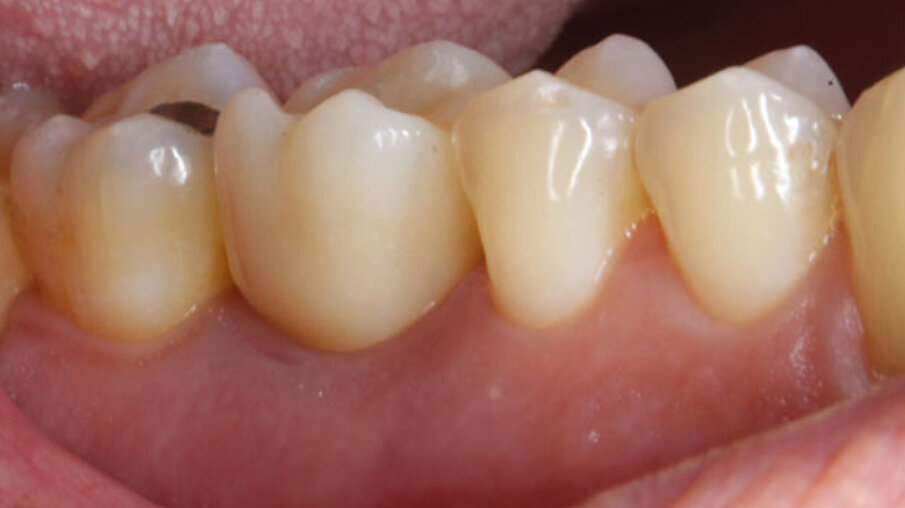

Dopo 3 mesi (Fig. 9) dall’inserimento del provvisorio è stata inserita la corona definitiva in zirconia. Per la sua realizzazione è stata utilizzata la scansione del dente prima dell’estrazione, ed è stata eseguita una scansione del tunnel mucoso guarito con iTero (Align Technology) (Figg. 9, 10). Dopo 2 anni i tessuti molli peri-implantari appaiono ben rappresentati e la radiografia evidenzia la stabilità dei tessuti duri (Figg. 11-13).

Fig. 11_Foto controllo (vista vestibolare) a 2 anni.

Fig. 13_Foto controllo (vista occlusale) a 2 anni.

Il seguente caso clinico mostra come la simultanea stabilizzazione del sito osseo e il riempimento del gap esistente con Bio-Oss, permette il mantenimento dei volumi orizzontali e verticali del sito9. La velocità e la comodità di eseguire una vite di guarigione customizzata, consente di migliorare il sigillo del perimetro mucoso e preservare la morfologia e il volume pre-esistenti. Sebbene l’impiego di viti di guarigione non anatomiche, ma di diametro maggiore, possa garantire un sigillo maggiore rispetto alle classiche viti di guarigione presenti in commercio, queste non permetterebbero di riprodurre esattamente i confini del sito come una vite di guarigione customizzata, ottenuta con metodica analogica e/o digitale19. La digitalizzazione consente una sostanziale riduzione dei tempi di esecuzione e una maggior personalizzazione del manufatto ottenuto, riproducendo al meglio la situazione esistente e riducendo al minimo il numero di interventi necessari, come avvitamenti e svitamenti durante le fasi di prova, per garantire il successo dell’impianto20. Utilizzando questa metodica, abbiamo ottenuto una guida per la maturazione dei tessuti molli, al fine di preparare la sede per l’inserimento della corona definitiva in una morfologia che non richiede ulteriori interventi o modifiche con protesi provvisorie o altri metodi. L’applicazione della matrice in collagene Fibro-Gide, precedentemente imbibita con il gel a base di polinucleotidi e acido ialuronico Regenfast, ha migliorato le fasi di guarigione, permettendo la formazione di una notevole quota di gengiva cheratinizzata perimplantare che fornisce un sicuro sigillo per difendersi dall’infiltrazione batterica. Regenfast è stato impiegato con l’obiettivo di potenziare e ottimizzare i processi rigenerativi. Recenti studi hanno evidenziato che i polinucleotidi, in sinergia con l’acido ialuronico, favoriscono la guarigione delle ferite21, la rigenerazione dei difetti ossei alveolari orizzontali22 e il trattamento delle tasche residue associate ai difetti infraossei23. La fase CAD gestisce la programmazione del pezzo, agendo sul profilo di emergenza per gestire la variazione dei tessuti molli. Conseguentemente, bisogna stimare un intervallo di produzione, che varia dai 45 ai 60 minuti a seconda del tipo di stampante e del materiale utilizzato.